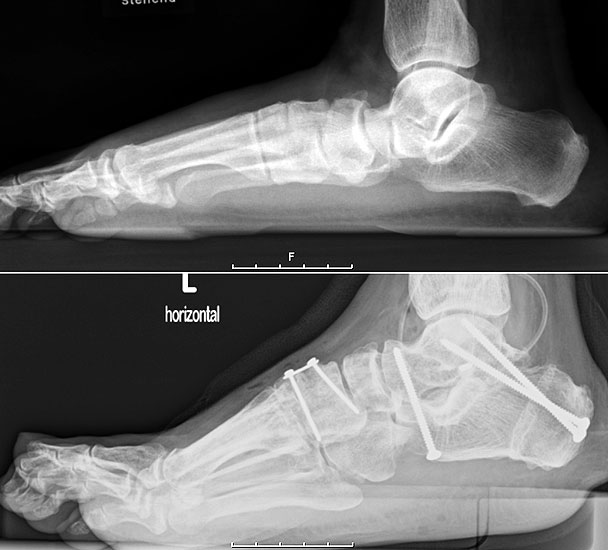

Stehende konventionelle Röntgenbilder eines Fußes mit Planovalgus Deformität Stadium II b dorsoplantar (dp) und seitlich. Auf der dp-Aufnahme zeigt sich die talo-calcaneare Divergenz, der gegenüber dem Kalkaneus nach anterior gleitende Talus und d

Abbildung 5

Stehende Aufnahmen des Fußes dorsoplantar (dp) und seitlich sowie des OSG anteroposterior (ap) sind die Grundlage der konventionellen Röntgendiagnostik (Abb. 5). Ergänzend werden gelegentlich die Rückfuβ-Alignement Aufnahme nach Saltzman 19 und Vergleichsaufnahmen der Gegenseite durchgeführt.

Radiologisches Beispiel einer fixierten Planovalgus Deformität Stadium III, 51 jähriger Patient. Stehendes präoperatives Röntgenbild und 1 Jahr postoperatives Röntgenbild des Fußes seitlich. Die Korrektur der Deformität umfaßte eine leicht korrigierende U

Abbildung 12